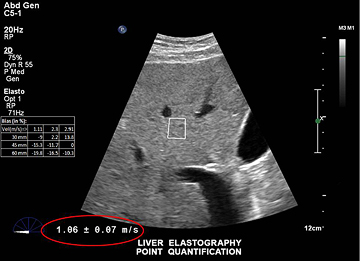

当社のエラストグラフィは、焦点式超音波ビームの音響放射力を使用して、肝臓内にShear waveを起こします。システムは、Shear waveの伝搬を検出し、速度測定を行い、分かりやすく表示します。